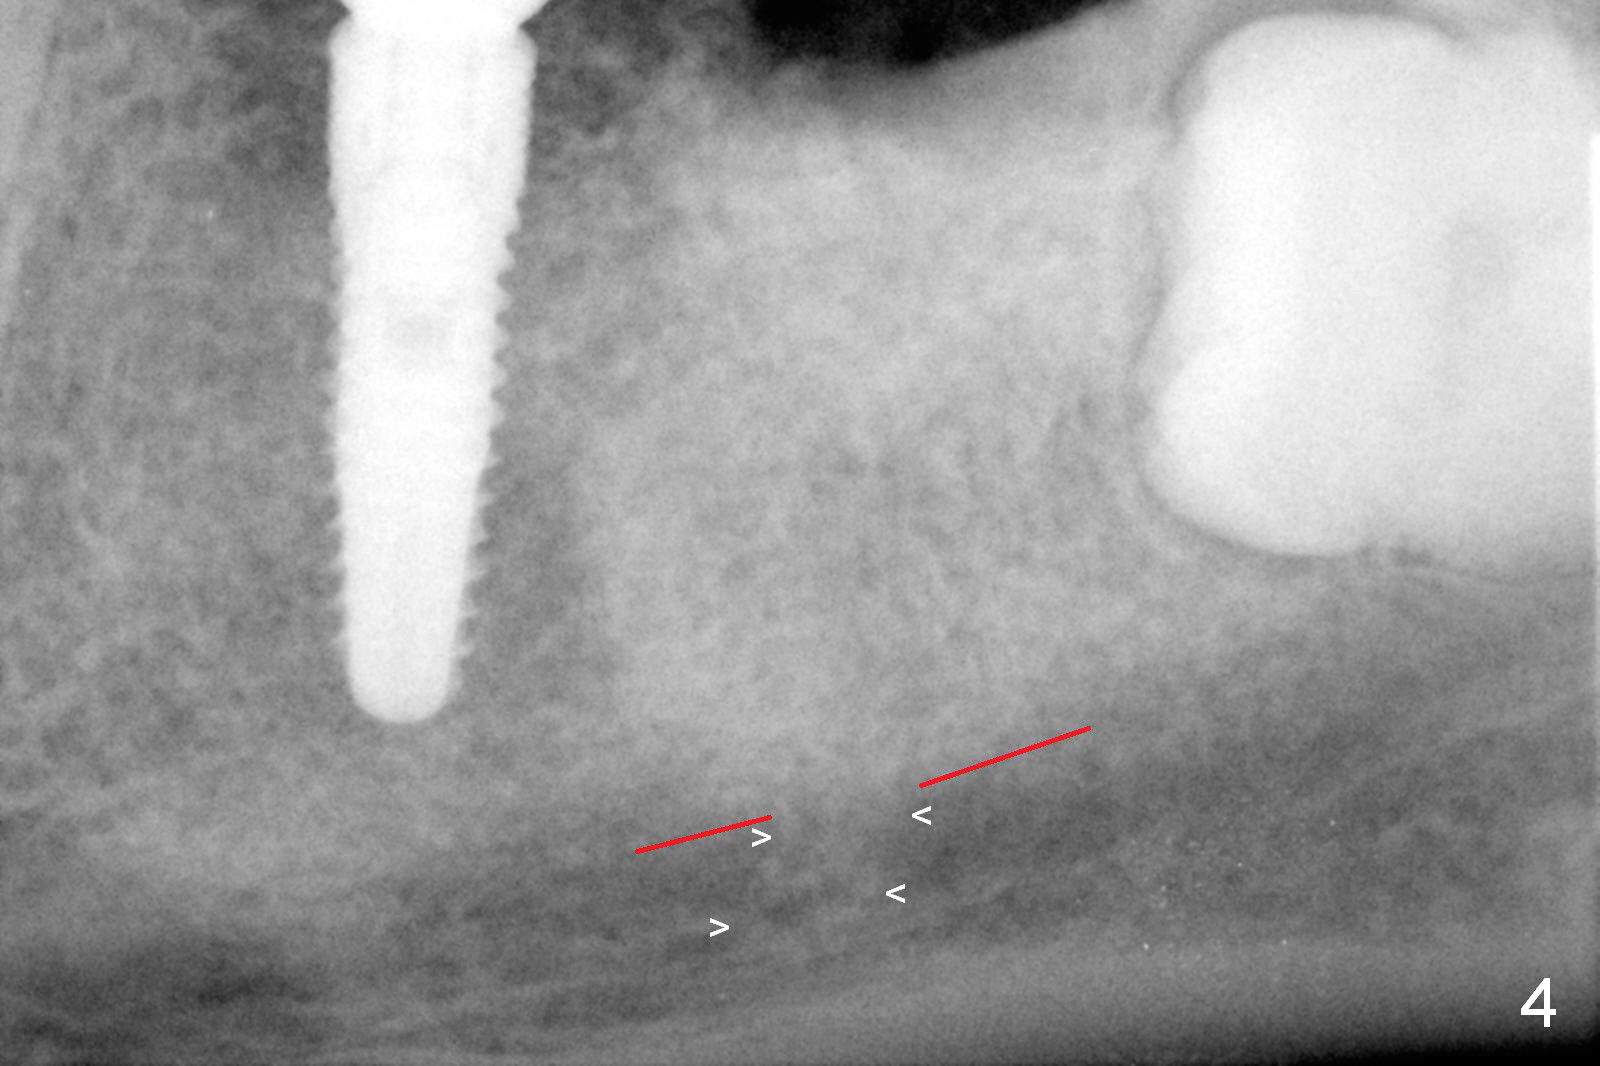

Infiltration anesthesia is enough for initial osteotomy at the site of #19 (Fig.1), but not for sectioning the tooth #18.  Block anesthesia has to be administered.  Fortunately it is safe to start osteotomy at #18 (~ 3 mm beyond the socket bottom, Fig.1 (red dashed line: the superior border of the Inferior Alveolar Canal (IAC))).  A 4.5x14 mm implant is stable at #19, while a 5x12 mm one at #18 is not (Fig.2).  Unfortunately bone graft has been placed.  When the implant is removed, a 4.5x14 mm drill is used to deepen the osteotomy for 2 mm.  The patient reports mild discomfort later on.  Hemorrhage occurs, which is stopped when the same implant is re-placed.  There is no stability.  The implant is removed (Fig.3,4).  More bone graft is placed, followed by collagen plug.  It appears that bone graft has been pushed into the IAC (Fig.4 arrowheads). Medro dose pak is prescribed.  In fact, no paresthesia is reported postop.